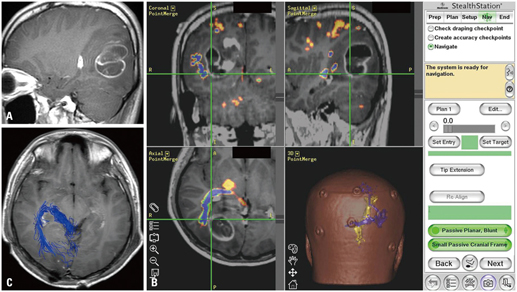

Brain tumor surgeries are of different types and could be done for both benign and malignant tumors. Traditionally, open surgery approach was followed based on the MRI/CT scans, however, our surgeons at IBS Hospital use Neuro- Navigation to perform real-time intra-operative guidance during brain surgery.

This increases the safety & precision of the surgery. Neuro- Navigation helps the surgeon to precisely localize the tumor and thus, limits the size of skull opening or craniotomy.

In Neuro- Navigation Guided Craniotomy, you will undergo Navigation screening protocol which assists the surgeon in planning tumor resection. Once you are shifted to the operating room, post anesthesia various fiducial markers are taped to the scalp and the orientation of these markers is used to register the computer containing the brain image. Once registration is completed, the computer can show the relationship of the surgical instruments to the imaged brain. In this procedure, either partial or complete removal of a tumor is undertaken.